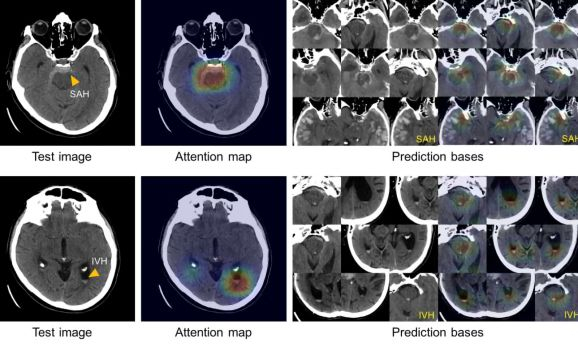

2019 同样见证了机器学习在健康领域的卓越发展。比如,麻省总医院(波士顿综合性医院)的研究者们开发了一个可以识别脑出血的人工智能系统 (https://venturebeat.com/2019/01/04/massachusetts-generals-ai-can-spot-brain-hemorrhages-as-accurately-as-humans/),精度可以达到人类水平。

人工智能系统分析的脑部扫描